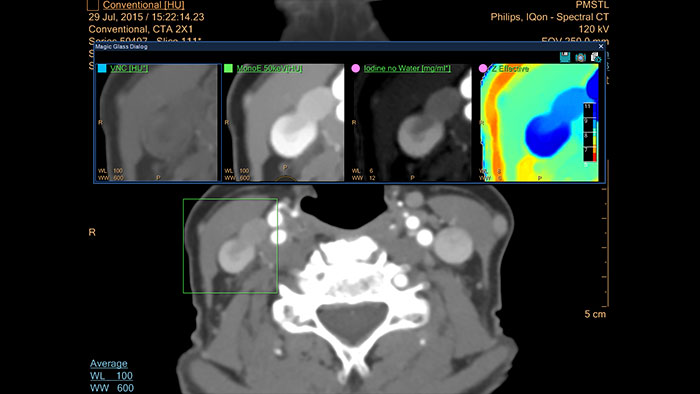

IQon Spectral CT* Functionality

The spectral viewer is optimized for analysis of spectral data sets from the IQon Spectral CT Scanner. Obtain a comprehensive overview of each patient quickly and easily, quantify quickly, and assist in diagnosis. It is designed to accommodate general spectral viewing needs with additional tools to assist in CT images analysis.

* IQon CT reconstruction provides a single DICOM entity containing sufficient information for retrospective analysis - Spectral Base Image (SBI). SBI contains all the spectrum of spectral results with no need for additional reconstruction or post-processing. Spectral applications are creating different spectral results from SBI.